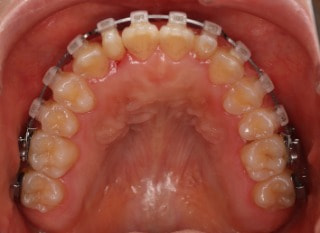

解説:下顎前突上顎劣勢長傾向で、上顎両側2番が矮小歯、右下2番先天欠如症例なので、上下前歯の幅径の比率を調節する必要があるケースです。(ご本人のご都合で治療中に来院できない期間がありました)

治療後(2年11ヶ月後)